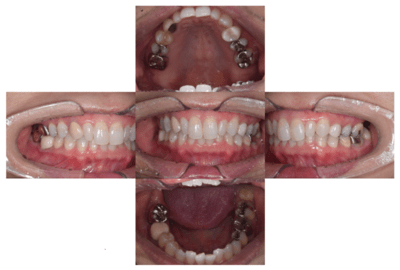

初診時の口腔内

説明:

初診時の口腔内です。かぶせ物があり、一見虫歯とはわからないです。

移植後

根管治療後

移植をし終わったところです。ワイヤーで3週間ほど固定します。その後根管治療を行い、かぶせ物をかぶせて治療終了になります。